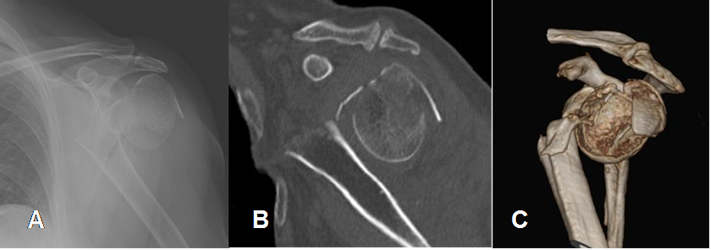

Fig 43. Fractura de húmero con cuerpo libre intra-articular.

A: Rx AP de hombro. Fractura impactada y conminuta de la cabeza humeral.

B: TAC axial y C: TAC reconstrucción coronal. Fragmento oseo libre intra-articular, en la parte postero-inferior de la glenoides.

Fig 44. Fractura de húmero reconstrucción 3 D.

A: Rx AP, B: TAC reconstrucción sagital y C: TAC reconstrucción 3 D. Fractura de la cabeza del húmero, con gran desplazamiento y angulación.